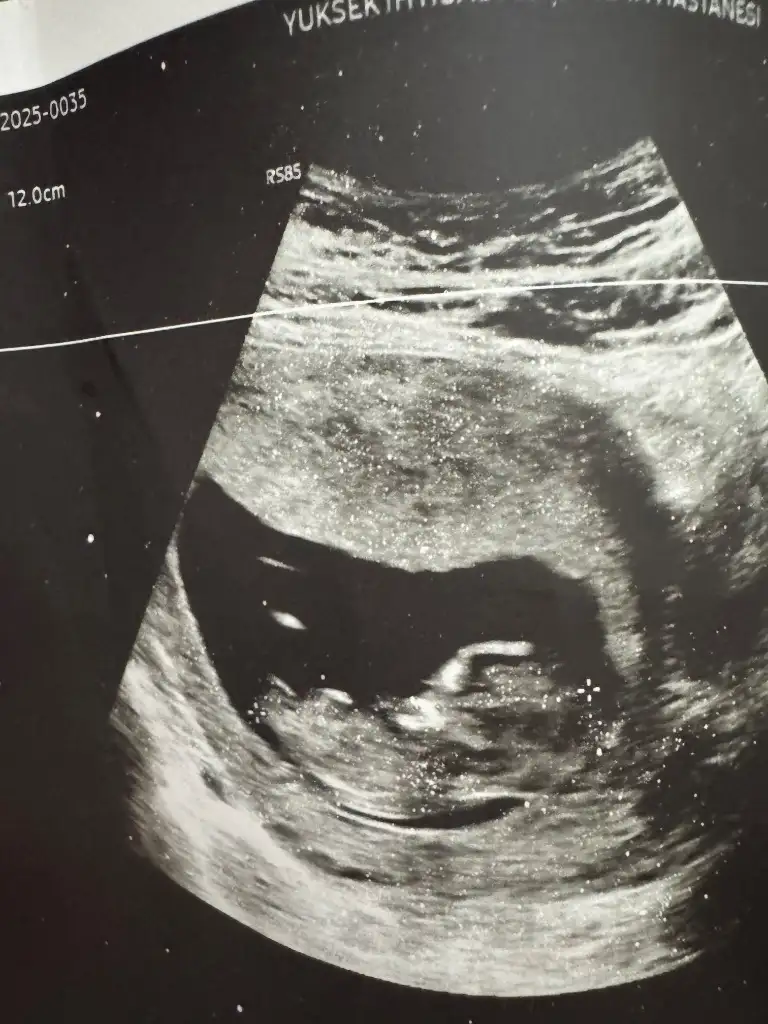

Merhaba kızlar 12 haftalık bebeğim cinsiyeti görebilen var mı doktor erkek gibi ama daha erken dedi

Kızlaaar 12+6dan selam olsun çok şükür burun kemiğini gördü ense kalınlığına normal dedi ama devlet hastanesi olduğu için cinsiyet hakkında bişry demedi bende hiç anlamam tahmin dahi yürütemem var mı içinizde tahmini olan 🙈

Ultrasonlardan ben de bir şey anlamıyorum ve yukarıda bir arkadaşın dediği gibi hepsinin duruşunu erkeğe benzetiyorum nedense😊Ama benim doktor bacaklarının yapısına bakarsak ve ortada çıkıntı da oluşmadığına göre kız olabilir demişti. Sizde de çıkıntı yok gibi. Ben de kız derdim tamamen tahmini olarak. Sağlıkla doğup mutlulukla büyüsün inşallah🧿💞

Bazen aklım almıyor buncacık beybide burun kemiğini görebiliyosun ama cinsiyet söylemiyosun😁bana kız gibi geldi hayırlı evlat olsun inşallah

Bana erkek gibi geldi omurilik yapısı grup erko dolacak yarabbiii 😀